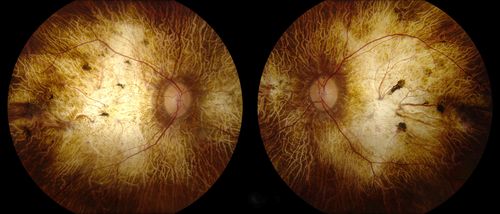

Chorodial Sclerosis

74 year old female diagnosed with Chorodial Sclerosis OU and ARMD OU. Va 20/400 OD 2'200 OS

Nicholas Leonard Carolina Eye Associates, P.A. North Carolina

Topcon TRC 50DX